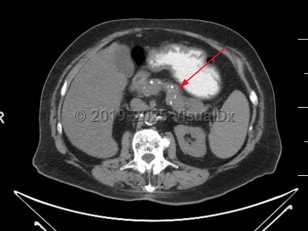

Chronic pancreatitis

The diagnosis of chronic pancreatitis can be challenging and relies on a combination of symptomatology, histologic, radiographic, and endoscopic findings. There is no single gold standard test to confirm the diagnosis. Some patients present with recurrent episodes of epigastric abdominal pain and pancreatic enzyme elevation, while others can present with asymptomatic diabetes mellitus and be found to have chronic pancreatitis. Regardless of the predisposing medical condition precipitating the development of chronic pancreatitis, radiographically, pancreatic atrophy and calcification with a dilated pancreatic duct are often but not always seen. Histologically, pancreatic fibrosis, duct distortion, and intra-ductal calcification are often but not always appreciated.